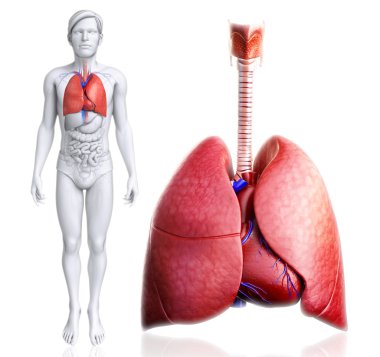

çizim, pulmoner dolaşım

ArkaplankişiİnsanKadınkanİlaçSolunumAvrupa DiliKardiyolojikalpdüzresim çalışmasıAkciğerSistemkemergemiüstünvenanatomiNormalauricletedavülarterAzalanyükselenCavaaortvena cavatorasikaşağıPulmonerventrikül20 30 yıldüz arka planKan damarıSolunum SistemiKan dolaşımıPnömolojiaortik kemerinen aortPulmoner dolaşımtorasik aortyükselen aortaPulmoner arterBenzer İçerikler